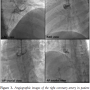

Physical examination revealed blood pressure of 140/90 mm Hg and a pulse of 109 beats/min. Auscultation showed clear lung sounds, normal heart beats, and no murmur or gallop. Twelve-lead electrocardiography revealed sinus tachycardia, and pathologic Q-wave in leads II, III, aVF (Figure 1). Laboratory analysis revealed creatine kinase (CK), 520 U/L (normal values: 24-170 U/L); CK-MB, 5.3 µg/mL (normal values: 0-6.6 µg/mL), troponin I, 0.037 ng/mL (normal values: <0.028 ng/mL), and brain natriuretic peptide, 34.8 pg/mL (normal values: 0-100 pg/mL). Even after careful, repetitive history taking and physical examination, he denied symptoms of chest pain or discomfort, since his back pain was so severe and intractable. However, under the diagnosis of recent myocardial infarction, we performed transthoracic echocardiography (TTE). TTE showed left ventricular (LV) ejection fraction of 51% with regional wall motion abnormalities — akinesis on basal segment of inferoseptum, severe hypokinesis on basal and mid-LV segments of inferior wall — corresponding to RCA (right coronary artery) territory ischemia.